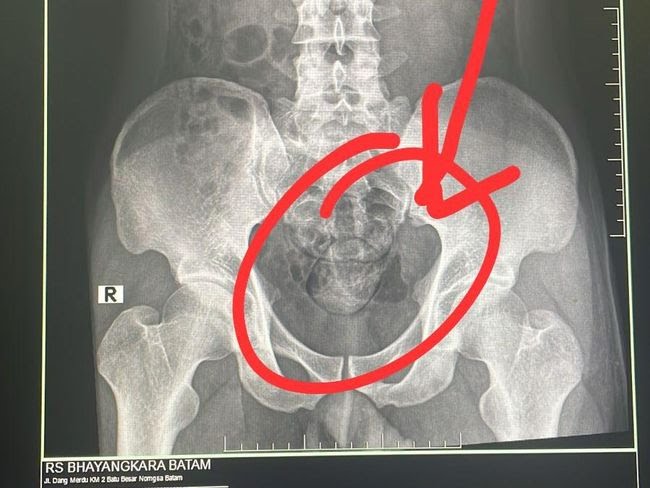

Pelaku kemudian dibawa anggota Subdit 2 Ditresnarkoba Polda Kepri ke RS Bhayangkara untuk dilakukan rontgen di bagian radiologi.

“Hasil dari rontgen ditemukan dua buah kapsul di dalam perut. Selanjutnya pelaku mengeluarkan dua kapsul tersebut di toilet RS Bhayangkara. Total berat narkoba jenis sabu sebanyak 100 gram,” ujarnya.